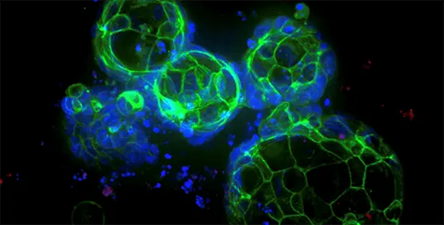

Breast cancer organoids

Image Credit: Molecular Devices UK Ltd

Clinically relevant tumor models are used to better understand the mechanism, examine tumor biomarkers, and test anticancer medicines.

Breast cancer organoids

Image Credit: Molecular Devices UK Ltd

Breast cancer patients’ survival rates depend heavily on early identification and treatment. This involves the use of therapeutically relevant tumor models to better understand the mechanism, identify tumor biomarkers, and screen anticancer medicines. Breast cancer tumoroids provide a platform for investigating tumor physiology and response to targeted therapy.